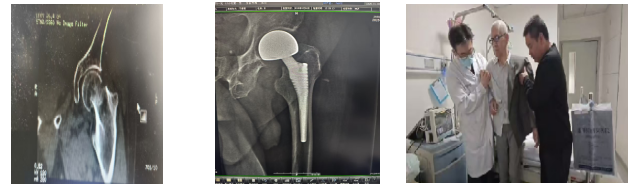

患者4:93岁的章爷爷,既往有双肺肺气肿,冠心病等多种内科疾病,未规律治疗,因摔伤致右侧股骨粗隆间骨折3天来院,患者年龄较高,手术、麻醉风险极高。

术前: 术后: